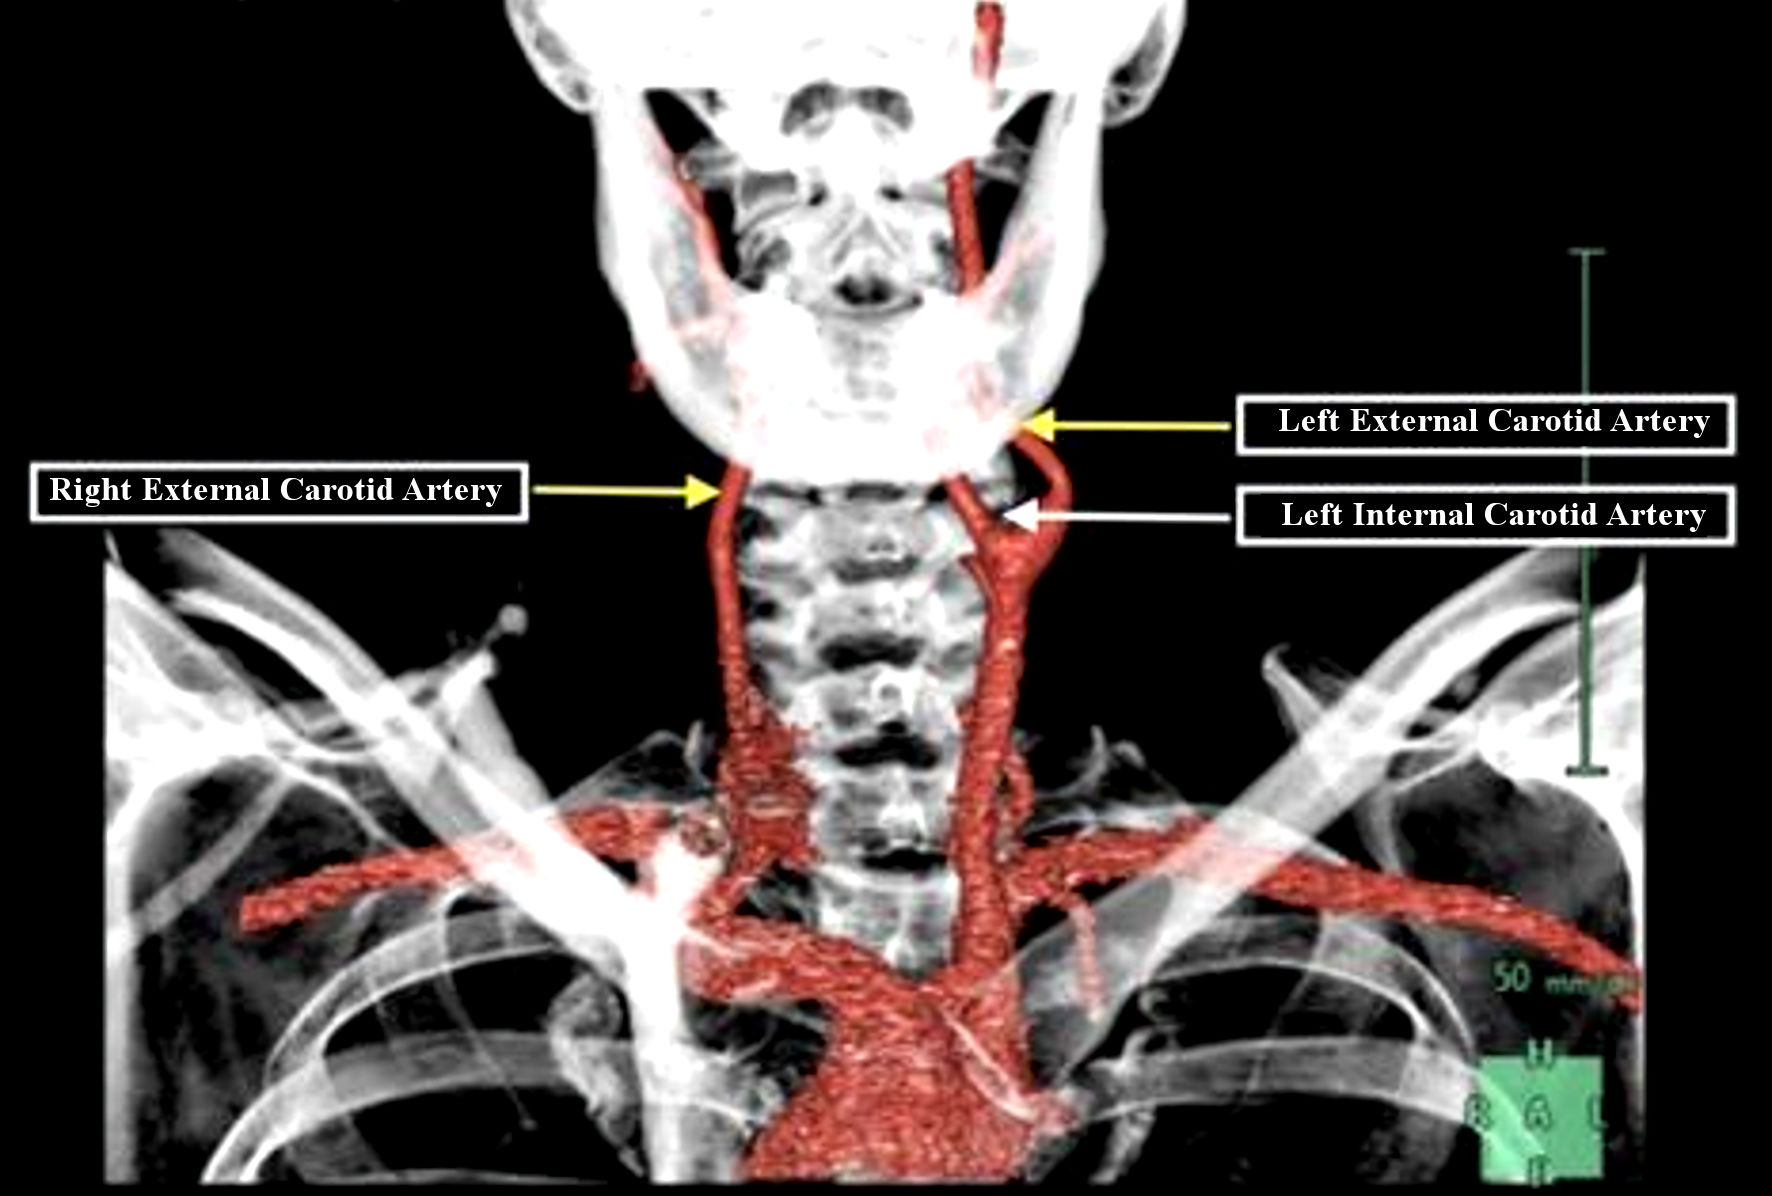

TCAR Procedure Savannah Vascular Institute

Carotid Artery Disease Stroke Victorian Vascular

Carotid Artery Disease CAD

Carotid Artery Stenosis Wikidoc

Carotid Arteries Eye Patient

Carotid Artery Stenosis Wikidoc

Occluded Carotid Artery Carotisverengung Swiss Surgery